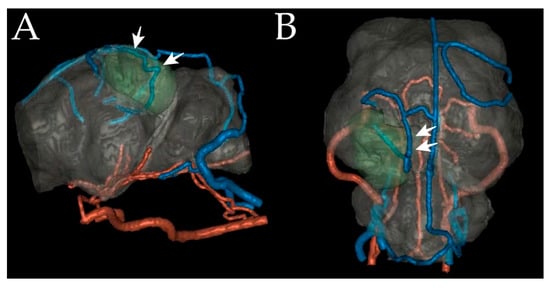

2.2. Images